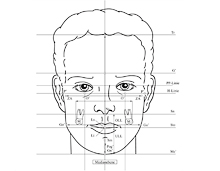

Geometrische Wachstumsanalyse der Seitröntgenaufnahme

Mit Hilfe der sog. Fernröntgenanalyse lässt sich nicht nur der Aufbau des Gesichtsschädels, sondern durch Überlagerungen mit älteren Aufnahmen auch das individuelle Wachstumsmuster erkennen. Dies ist von unschätzbarem Wert für die Steuerung des Wachstums während der Behandlung.

Mit Hilfe der sog. Fernröntgenanalyse lässt sich nicht nur der Aufbau des Gesichtsschädels, sondern durch Überlagerungen mit älteren Aufnahmen auch das individuelle Wachstumsmuster erkennen. Dies ist von unschätzbarem Wert für die Steuerung des Wachstums während der Behandlung.

Fotografische Analyse des Gesichtsprofils und des Lachlinien-Verlaufes

Kinnprofil, Lippenprofilverlauf und -volumen, ja sogar der Verlauf und die Tiefe perioraler Falten hängen stark von der genauen Stellung der Kiefer und der Zähne ab. Bevor wir Zahn- und Kieferpositionen durch orthopädische Behandlung verändern, ist es für uns unabdingbar, eine sorgfältige Profilanalyse vorzunehmen und die Ergebnisse bei der Planung der Behandlung maßgeblich zu berücksichtigen.

Kinnprofil, Lippenprofilverlauf und -volumen, ja sogar der Verlauf und die Tiefe perioraler Falten hängen stark von der genauen Stellung der Kiefer und der Zähne ab. Bevor wir Zahn- und Kieferpositionen durch orthopädische Behandlung verändern, ist es für uns unabdingbar, eine sorgfältige Profilanalyse vorzunehmen und die Ergebnisse bei der Planung der Behandlung maßgeblich zu berücksichtigen.